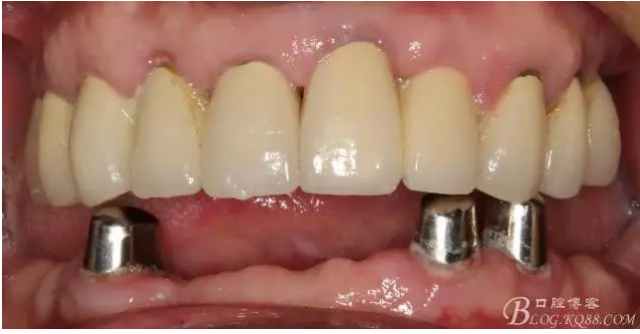

修復(fù)后照片,

患者的口腔衛(wèi)生保持的不好,有大量的軟垢附著,

最近復(fù)查的照片,牙周維護(hù)好一些了,畢竟是一個(gè)80歲的老爺爺了,每次來拄著拐,還要跟著很多人攙扶著過來很不容易了。